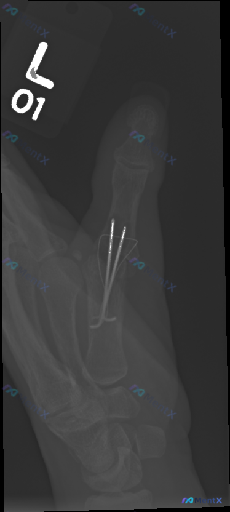

整理了一份左手拇指术后复查的影像资料,先看第一印象: - 左手拇指斜位X光,第一掌指关节(MCP)有两枚克氏针固定,穿过近节指骨基底到第一掌骨头 - 骨折线处可见骨痂形成,骨皮质尚连续,没看到明显骨质破坏或脱位 - 周围软组织没报明显弥漫性肿胀,籽骨位置也正常 报告首先提示是“术后修复状态”,但这份...

网上看到一份左手拇指的影像资料,描述整理如下,大家一起讨论下: - 这是一张左拇指的侧位/斜位X光片,影像显示清晰 - 可见拇指近节指骨及掌指关节附近有内固定装置(钢板+多枚螺钉,关节附近还有一枚中空/加压装置) - 近节指骨有陈旧性骨折线迹象,骨折断端对位对线尚可 - 无明显螺钉松动、断裂或钢板移...